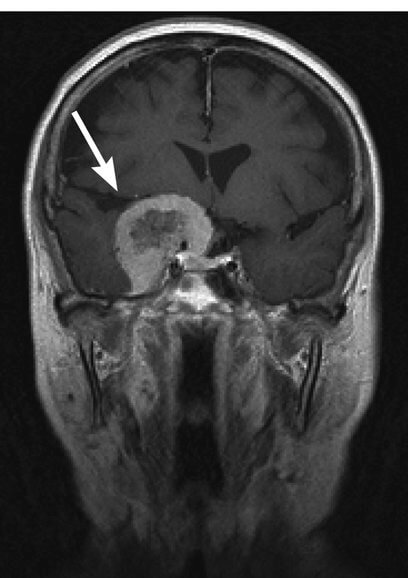

(画像引用元 https://health.goo.ne.jp/medical/108A0300)

髄膜腫(ずいまくしゅ)は脳腫瘍のなかで最も多い脳腫瘍です。一般的に脳を覆うくも膜の細胞から発生し、90%以上は良性腫瘍です。

多くは脳実質外に存在しますが、約30%は脳表面を覆う軟膜を破壊し、脳浮腫や脳内伸展を認めます。女性に多く、原因として遺伝や放射線、女性ホルモンなどの関与が示唆されているが、多くは原因不明です。

腫瘍の生じる部位によって、様々な名称がありますが、代表的なものは円蓋部髄膜腫、傍矢静洞髄膜腫、大脳鎌髄膜腫などです。